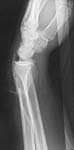

Ace makes some plates, the PERI set which has a particularly good implant for this type of fracture. The meta plate which has 2 different size flares. The smaller one fits well on the radius even though it was originally designed for the distal tibia. It comes in multiple sizes. These plates were designed by Drs. Bone and Sanders.

Below is an example.